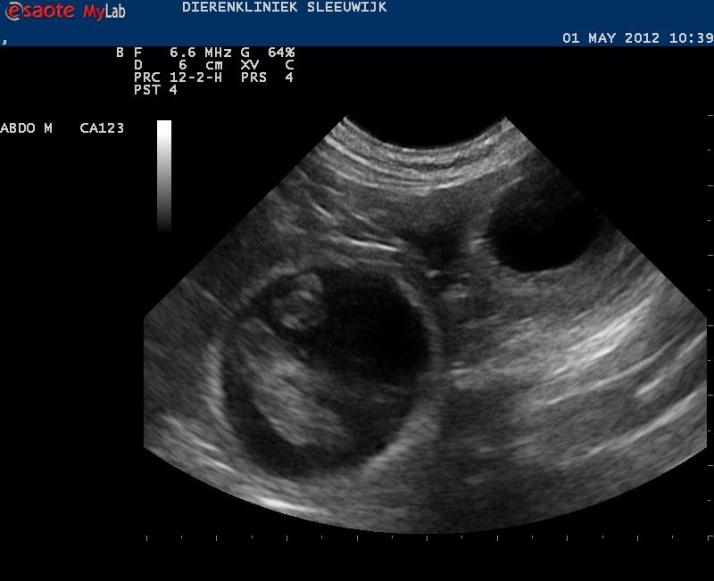

De afspraak voor de echo is gemaakt, ik hoop dat we begin volgende week het eerste bewijs van leven kunnen tonen.

Aan het eind van de week zijn ze 30 mm groot. De hoeveelheid vruchtwater neemt ook toe.